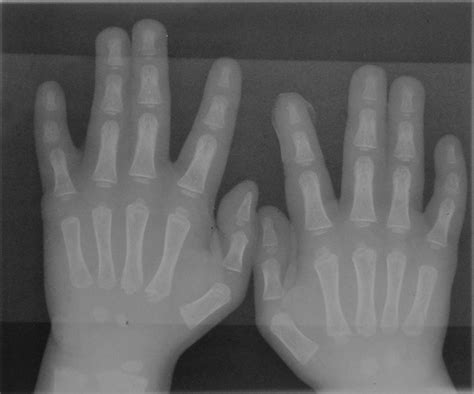

Polidattilia significa dita delle mani o dei piedi supplementari. Nella maggioranza dei casi la duplicazione coinvolge il mignolo o il quinto dito dei piedi oppure il pollice o l’alluce. Questa condizione può manifestarsi in modi molto diversi tra loro: il dito supplementare della mano o del piede può essere solo un’escrescenza di tessuto carnoso o un dito perfettamente funzionante, con terminazioni nervose, ossa e articolazioni proprie. La polidattilia può verificarsi da sola o nell’ambito di una sindrome genetica come la sindrome di Apert. Quando difetti simili sono presenti in altri familiari del bambino o se i medici sospettano una sindrome genetica, il bambino può essere valutato da un genetista, un medico specializzato in genetica, ovvero la scienza dei geni e del modo in cui certe qualità o tratti vengono trasmessi dai genitori alla prole.

Per rimuovere un dito della mano o del piede supplementare si può intervenire chirurgicamente. La scelta del momento opportuno e della tecnica dipende dalla complessità del dito aggiuntivo, specialmente se questo possiede strutture ossee e articolari complete. La diagnosi può iniziare molto presto: prima della nascita i medici sono talvolta in grado di diagnosticare questi difetti durante gli esami ecografici di routine raccomandati per tutte le gestanti. Dopo la nascita, in genere il medico prescrive radiografie e può eseguire altri esami di diagnostica per immagini per stabilire quali ossa sono interessate dalla duplicazione.